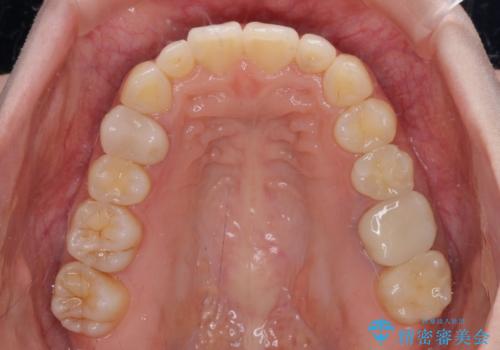

- 上顎前歯の突出感を気にして来院された患者様です。

下顎前歯2本が先天欠損しており、上顎歯列に対して、下顎歯列がアンバランスに小さい状況でした。

左右上顎側切歯2本が矮小歯であるため、上顎の抜歯ではなく、IPR(歯と歯の間を削る)と歯列全体の後方移動によってバランスを整えることとしました。

歯列のバランスが悪く、インビザライン矯正特有の奥歯の噛みにくさがなかなか改善されず、治療期間が長期化してしまいました。